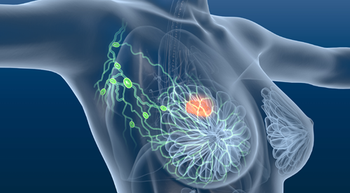

The DESTINY-Breast11 trial found neoadjuvant T-DXd followed by THP improved pathologic complete response vs ddAC-THP in high-risk, HER2-positive early breast cancer.

Long-term NATALEE data show adjuvant ribociclib plus an aromatase inhibitor (AI) improves invasive disease–free survival vs AI alone in HR+, HER2– early breast cancer.